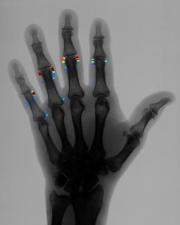

We propose a computer based method that performs the quantification by means of automated image analysis and pattern recognition. The goal is to fully automatically identify the bones of the hand/wrist and extract exact quantitative information about the extent of the erosions caused by rheumatoid arthritis based on a radiograph.